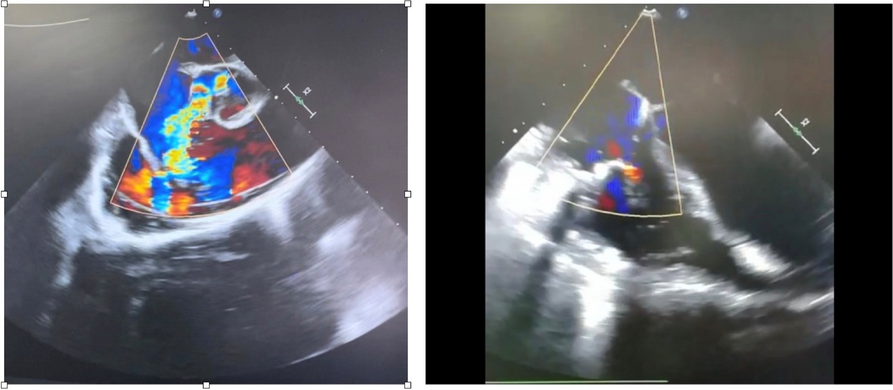

A few hours after the admission in ICU he reported a blunt abdominal pain, mainly on the right side, nausea and the exams showed increased amylase levels, urologists excluded any surgical involvement of pancreatic tissue and suspected a transient sphincter of Oddi dysfunction [3]. After one night in ICU he was transferred to the urology ward due to his clinical stability, even though Amylase peaked at 2340 U/l. Two days later abdominal pain increased to severe, with characteristics of peritonism and increased inflammatory markers. An abdomen-thorax CT scan revealed acute pancreatitis (AP) (Figure 1) and he was transferred to ICU. He started a standard treatment for acute pancreatitis and antibiotic therapy [4].

Fig. 1 (abstract A21).

See text for description